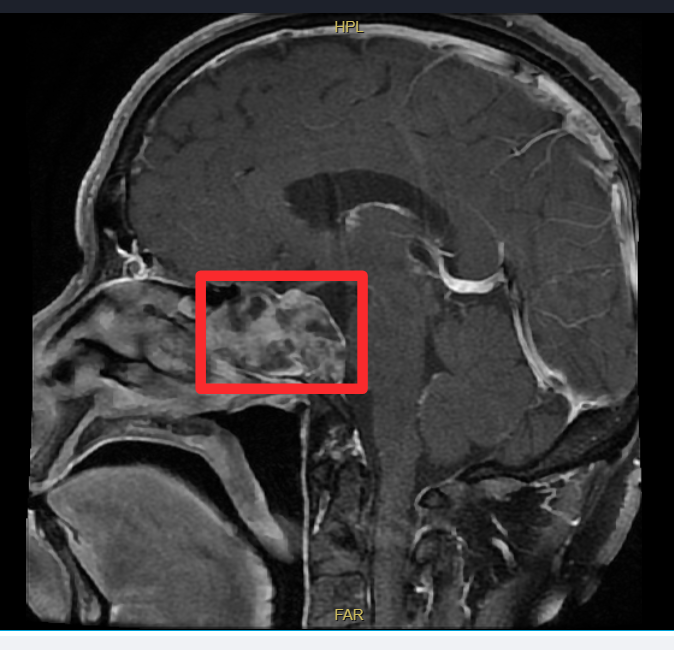

怀着一线希望,陈先生来到了中大医院,找到了擅长鼻及鼻颅底手术的孙宝宾副主任医师。经过详细的术前检查和评估,孙宝宾副主任医师团队认为肿瘤很可能起源于颅底的蝶窦区域,并已对周围骨质造成了侵蚀。为明确肿瘤性质,团队为其实施鼻内镜下蝶窦肿物活检术。术后病理报告确诊为脊索瘤。

经过周密的术前准备,一场在生命禁区“绣花”的手术开始了。孙宝宾副主任医师团队采用先进的鼻内镜微创技术,术中发现肿瘤充满蝶窦腔,起源于斜坡,呈胶冻状,已破坏窦底与斜坡骨质,甚至与深处的脑膜发生了粘连。每一步操作都如履薄冰,稍有不慎就可能引发大出血或神经损伤。

凭借对鼻颅底解剖结构的深刻认知与娴熟内镜操作技巧,孙宝宾副主任医师先开放手术通道、充分暴露肿瘤,再细致剥离肿瘤组织与重要脑膜结构,随后整块切除肿瘤,并以等离子烧灼干净肿瘤基底部。术中脑膜未破裂,为术后恢复奠定坚实基础。